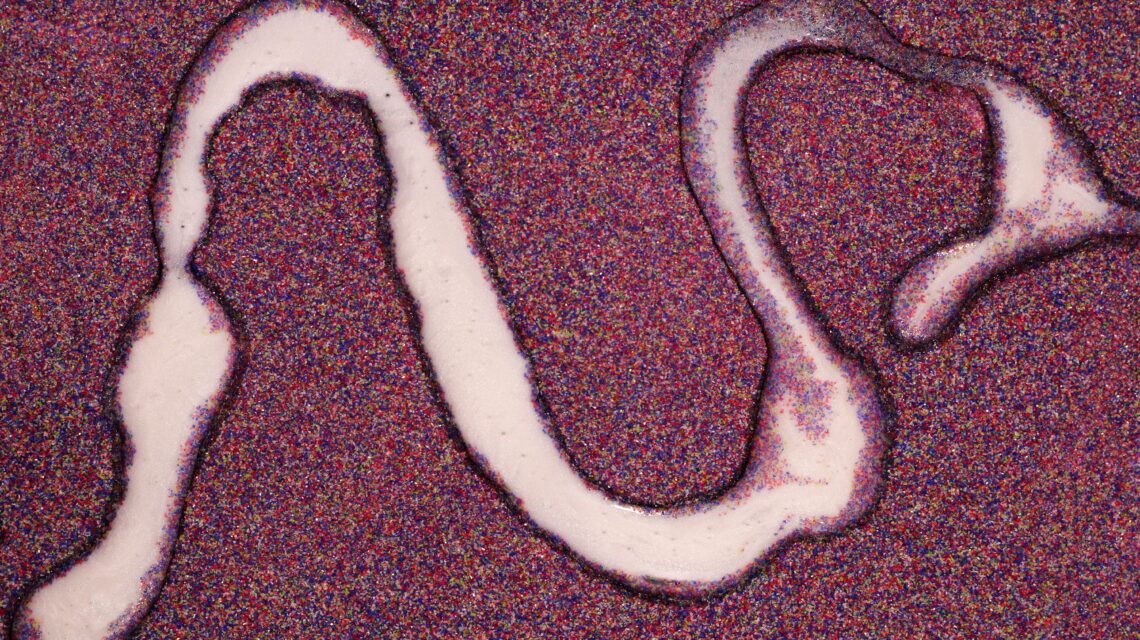

Les parasites intestinaux : ces intrus qui perturbent la digestion et la vitalité

Les parasites intestinaux ne se contractent pas seulement à l’étranger. Ils sont parfois présents dans l’eau, les fruits et légumes, ou transmis par les animaux domestiques.

Chez une personne déjà fragilisée par l’inflammation de l’endométriose, ils peuvent amplifier la fatigue, les douleurs et les troubles digestifs.

- Oxyures : petits vers blancs provoquant démangeaisons anales et troubles du sommeil.